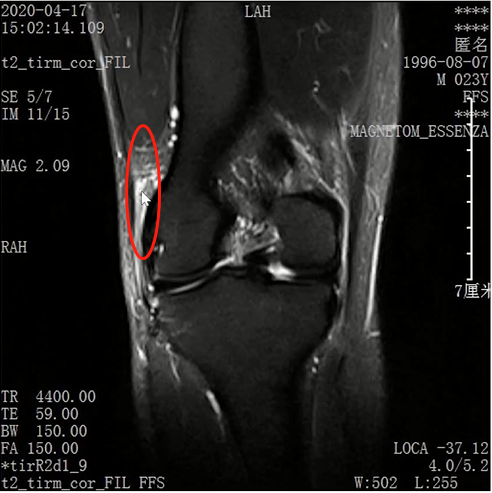

Lisfranc损伤在多发伤病人中常常容易漏诊,大约为 20-30%的漏诊率!